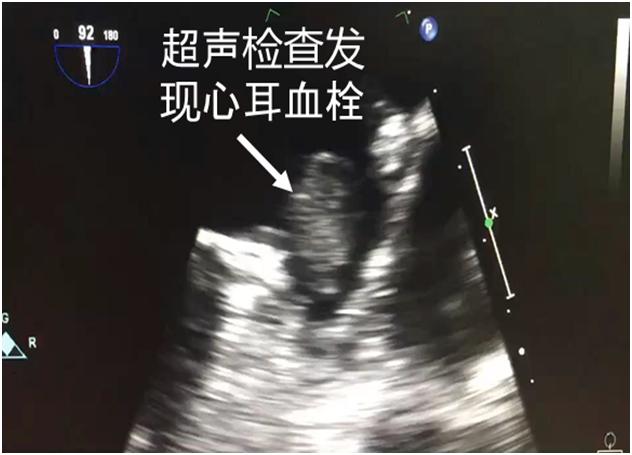

中国是脑卒中高发大国,房颤是脑卒中最重要的病因之一。房颤的治疗目标是恢复窦性心律和预防栓塞事件的发生。据仁济医院宝山分院执行主任黄剑锋教授介绍,接受“一站式”介入治疗的患者72岁高龄,同时合并冠心病和心房颤动,冠脉造影提示三支冠脉病变,临床评估CHA2DS2-VASc评分5分,HASBLED评分4分,是一个同时存在高血栓栓塞和高出血风险的患者。在术前积极完善各项辅助检查,评估患者的适应症,与患者及家属充分沟通,进行术前讨论,考虑到患者高龄,为减少麻醉意外风险,增加手术耐受程度,最终决定在局部麻醉下实施ICE指导下“经皮左心耳封堵术+射频消融”一站式治疗技术。

心腔内超声(ICE),即心腔内超声成像技术,是一项术中实时超声监测技术,临床应用优势明显,尤其是老年患者,行左心耳封堵术的同时可以避免全麻后遗症、术后难苏醒等问题。且能保证患者在比较平静的状态下顺利进行手术。同样,ICE也适用于食道超声检查有禁忌的患者。房颤“一站式”介入治疗的患者,ICE还能代替多极导管进行左房精确建模,提高手术安全性和减少射线量。